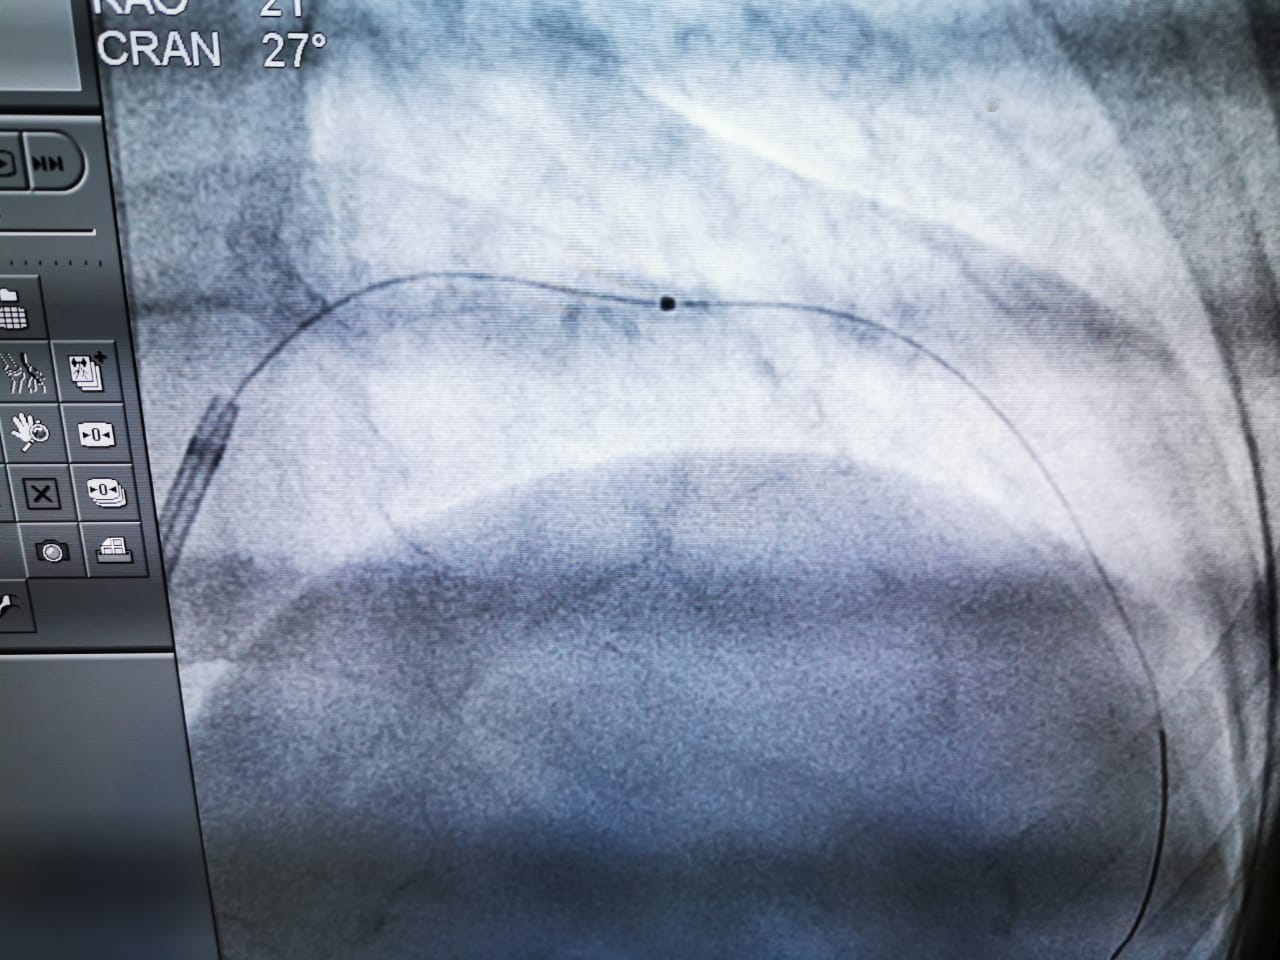

It gives us immense pleasure to have witnessed India’s First laser atherectomy (Lad uncrossable with balloon, Laser 0.9 and 1.4 ELCA) at JNM hospital Raipur chattisgargh with Dr Smit Srivastava, proctored by Dr. Arun Kalyanasundaram. We thank everyone who participated in this event and made it possible!